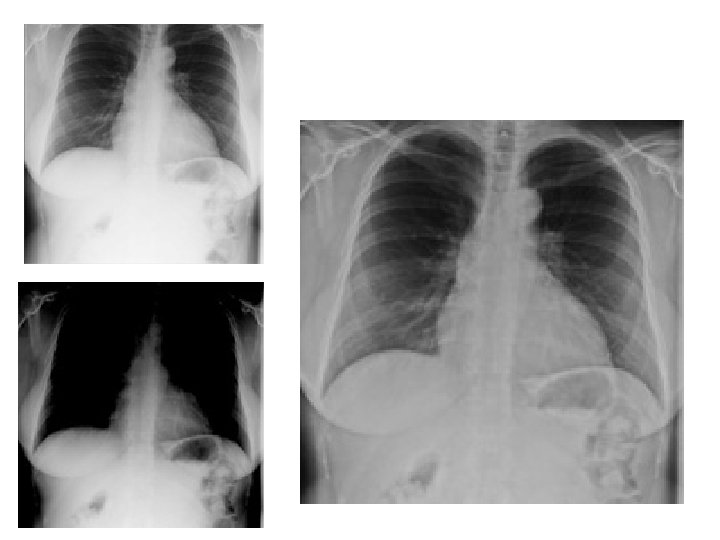

Film screen • • Radiographic Density Overall blackening of the radiographic image as a result of the energy deposited inthe film emulsion.

Film screen Radiographic Contrast / Grayscale • The difference between two adjacent • radiographic densities in the image. • • The overall number of density shades present in the image.

Image-forming x-rays • Two kinds of photons are responsible for the OD and contrast on an image: Photons that pass through without interacting and those that are scattered though Compton. • X-rays that exit the patient are remnant and those that interact with the IR are image-forming.